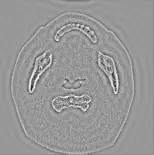

- 濾波後頻譜影像(右下):在頻譜空間進行濾波(Filtering)。可明顯觀察到頻譜正中心的亮點被打黑(低頻成分被濾除),而周圍的訊號被保留下來。此種操作為典型的高通濾波(High-pass filtering)。

- 反傅立葉轉換結果(左下問號處):高通濾波後的頻譜經反傅立葉轉換(Inverse Fourier Transform)回到空間域。因為去除了低頻訊號(失去整體的亮度與對比漸層),並保留了高頻訊號,預期得到的影像會突顯各個組織邊界的輪廓,形成邊緣強化的效果,且平滑組織區域會呈現均勻的灰色。

- 選項 A:影像失去原始的整體灰階分布,背景與平滑軟組織呈現均勻的灰色,但骨骼、空氣等組織的交界處呈現極為明顯的亮暗輪廓線。此即為保留高頻、濾除低頻的「高通濾波」結果,完全符合題目頻譜圖的改變。

本題的解題關鍵在於觀察「Filtering in the Frequency Domain」這張圖。該圖中心的低頻區域呈現黑色(表示被濾除或數值降至零),而外圍的高頻區域被保留,這是一個標準的高通濾波器。低頻訊號負責提供影像的背景灰階與大範圍的對比;高頻訊號則提供影像邊緣與急遽變化的細節。

經過高通濾波後,影像會失去整體的對比漸層(低頻消失),只留下邊緣特徵(高頻保留),在視覺上會表現為一張灰色底圖上帶有明顯邊界線條的影像。選項 A 完美吻合高通濾波(邊緣強化)的特徵,因此為正確答案。